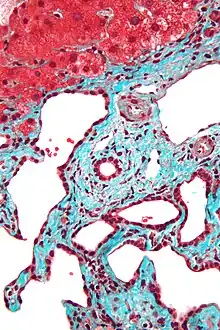

Micrograph of a bile duct hamartoma. Trichrome stain, high magnification Micrograph of a bile duct hamartoma. Trichrome stain, high magnification